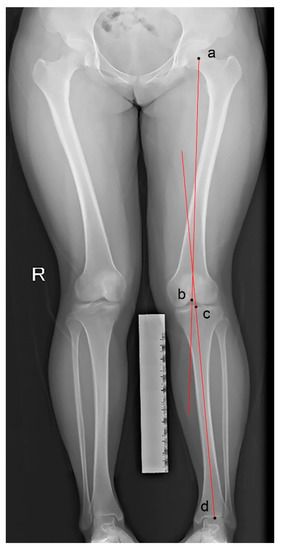

2.4.5. Coronal Malalignment